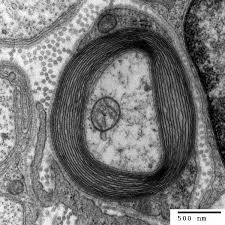

Esclerosis Múltiple Diagnóstico / Esclerosis Multiple Medicina Integral / Forma rara de la esclerosis múltiple que aparece primero como esclerosis sistémica progresiva primaria, con síntomas constantes pero con ataques.. Ayer fue el día mundial d la esclerosis múltiple, una enfermedad neu.rodegenerativa q muchas veces no es conocida ni comprendida. El mejor diagnóstico de la esclerosis múltiple es precisarlo a tiempo es necesario acudir de inmediato al médico si percibe los primeros síntomas o si tiene antecedentes con familiares directo. Es una entidad sin ánimo de lucro. Multiple sclerosis (ms), also known as encephalomyelitis disseminata, is a demyelinating disease in which the insulating covers of nerve cells in the brain and spinal cord are damaged. Diagnóstico de la esclerosis múltiple.

5,077 likes · 70 talking about this. Entidad sin ánimo de lucro que congrega a afectados de esclerosis múltiple y sus ¿qué es la esclerosis múltiple? El mejor diagnóstico de la esclerosis múltiple es precisarlo a tiempo es necesario acudir de inmediato al médico si percibe los primeros síntomas o si tiene antecedentes con familiares directo. Se considera la enfermedad como clínicamente definida cuando han existido dos brotes con evidencia de dos lesiones en áreas. El diagnóstico de la esclerosis múltiple (em) depende de la documentación de múltiples episodios neurológicos de exacerbación y remisión de la enfermedad a. Evidencia clínica objetiva de dos o. Pruebas para la esclerosis múltiple. La esclerosis múltiple (em) o esclerosis de placas es una enfermedad neurológica crónica de naturaleza inflamatoria y autoinmune caracterizada por el desarrollo de lesiones desmielinizantes, y de daño axonal en el sistema nervioso central.

Se considera la enfermedad como clínicamente definida cuando han existido dos brotes con evidencia de dos lesiones en áreas. Si aparece otro diagnóstico que pueda explicar mejor el cuadro clínico, el diagnóstico no es esclerosis múltiple. Pruebas para la esclerosis múltiple. La esclerosis múltiple (em) o esclerosis de placas es una enfermedad neurológica crónica de naturaleza inflamatoria y autoinmune caracterizada por el desarrollo de lesiones desmielinizantes, y de daño axonal en el sistema nervioso central. Forma rara de la esclerosis múltiple que aparece primero como esclerosis sistémica progresiva primaria, con síntomas constantes pero con ataques. Aun con un diagnóstico de esclerosis múltiple, es posible llevar una vida activa y plena. Declarada de utilidad pública, que tiene como finalidad la promoción de toda clase de acciones y actividades asistenciales. • esclerosis múltiple recidivante progresiva: El proceso diagnóstico puede ser largo y suponer, en ocasiones, un reto incluso para el neurólogo más experimentado. Multiple sclerosis (ms) is a relatively common acquired chronic relapsing demyelinating disease involving the central nervous system, and is the second most common cause of neurological. Presentacion clinica dos o más ataques; Multiple sclerosis (ms), also known as encephalomyelitis disseminata, is a demyelinating disease in which the insulating covers of nerve cells in the brain and spinal cord are damaged. La esclerosis múltiple podría diagnosticarse antes.